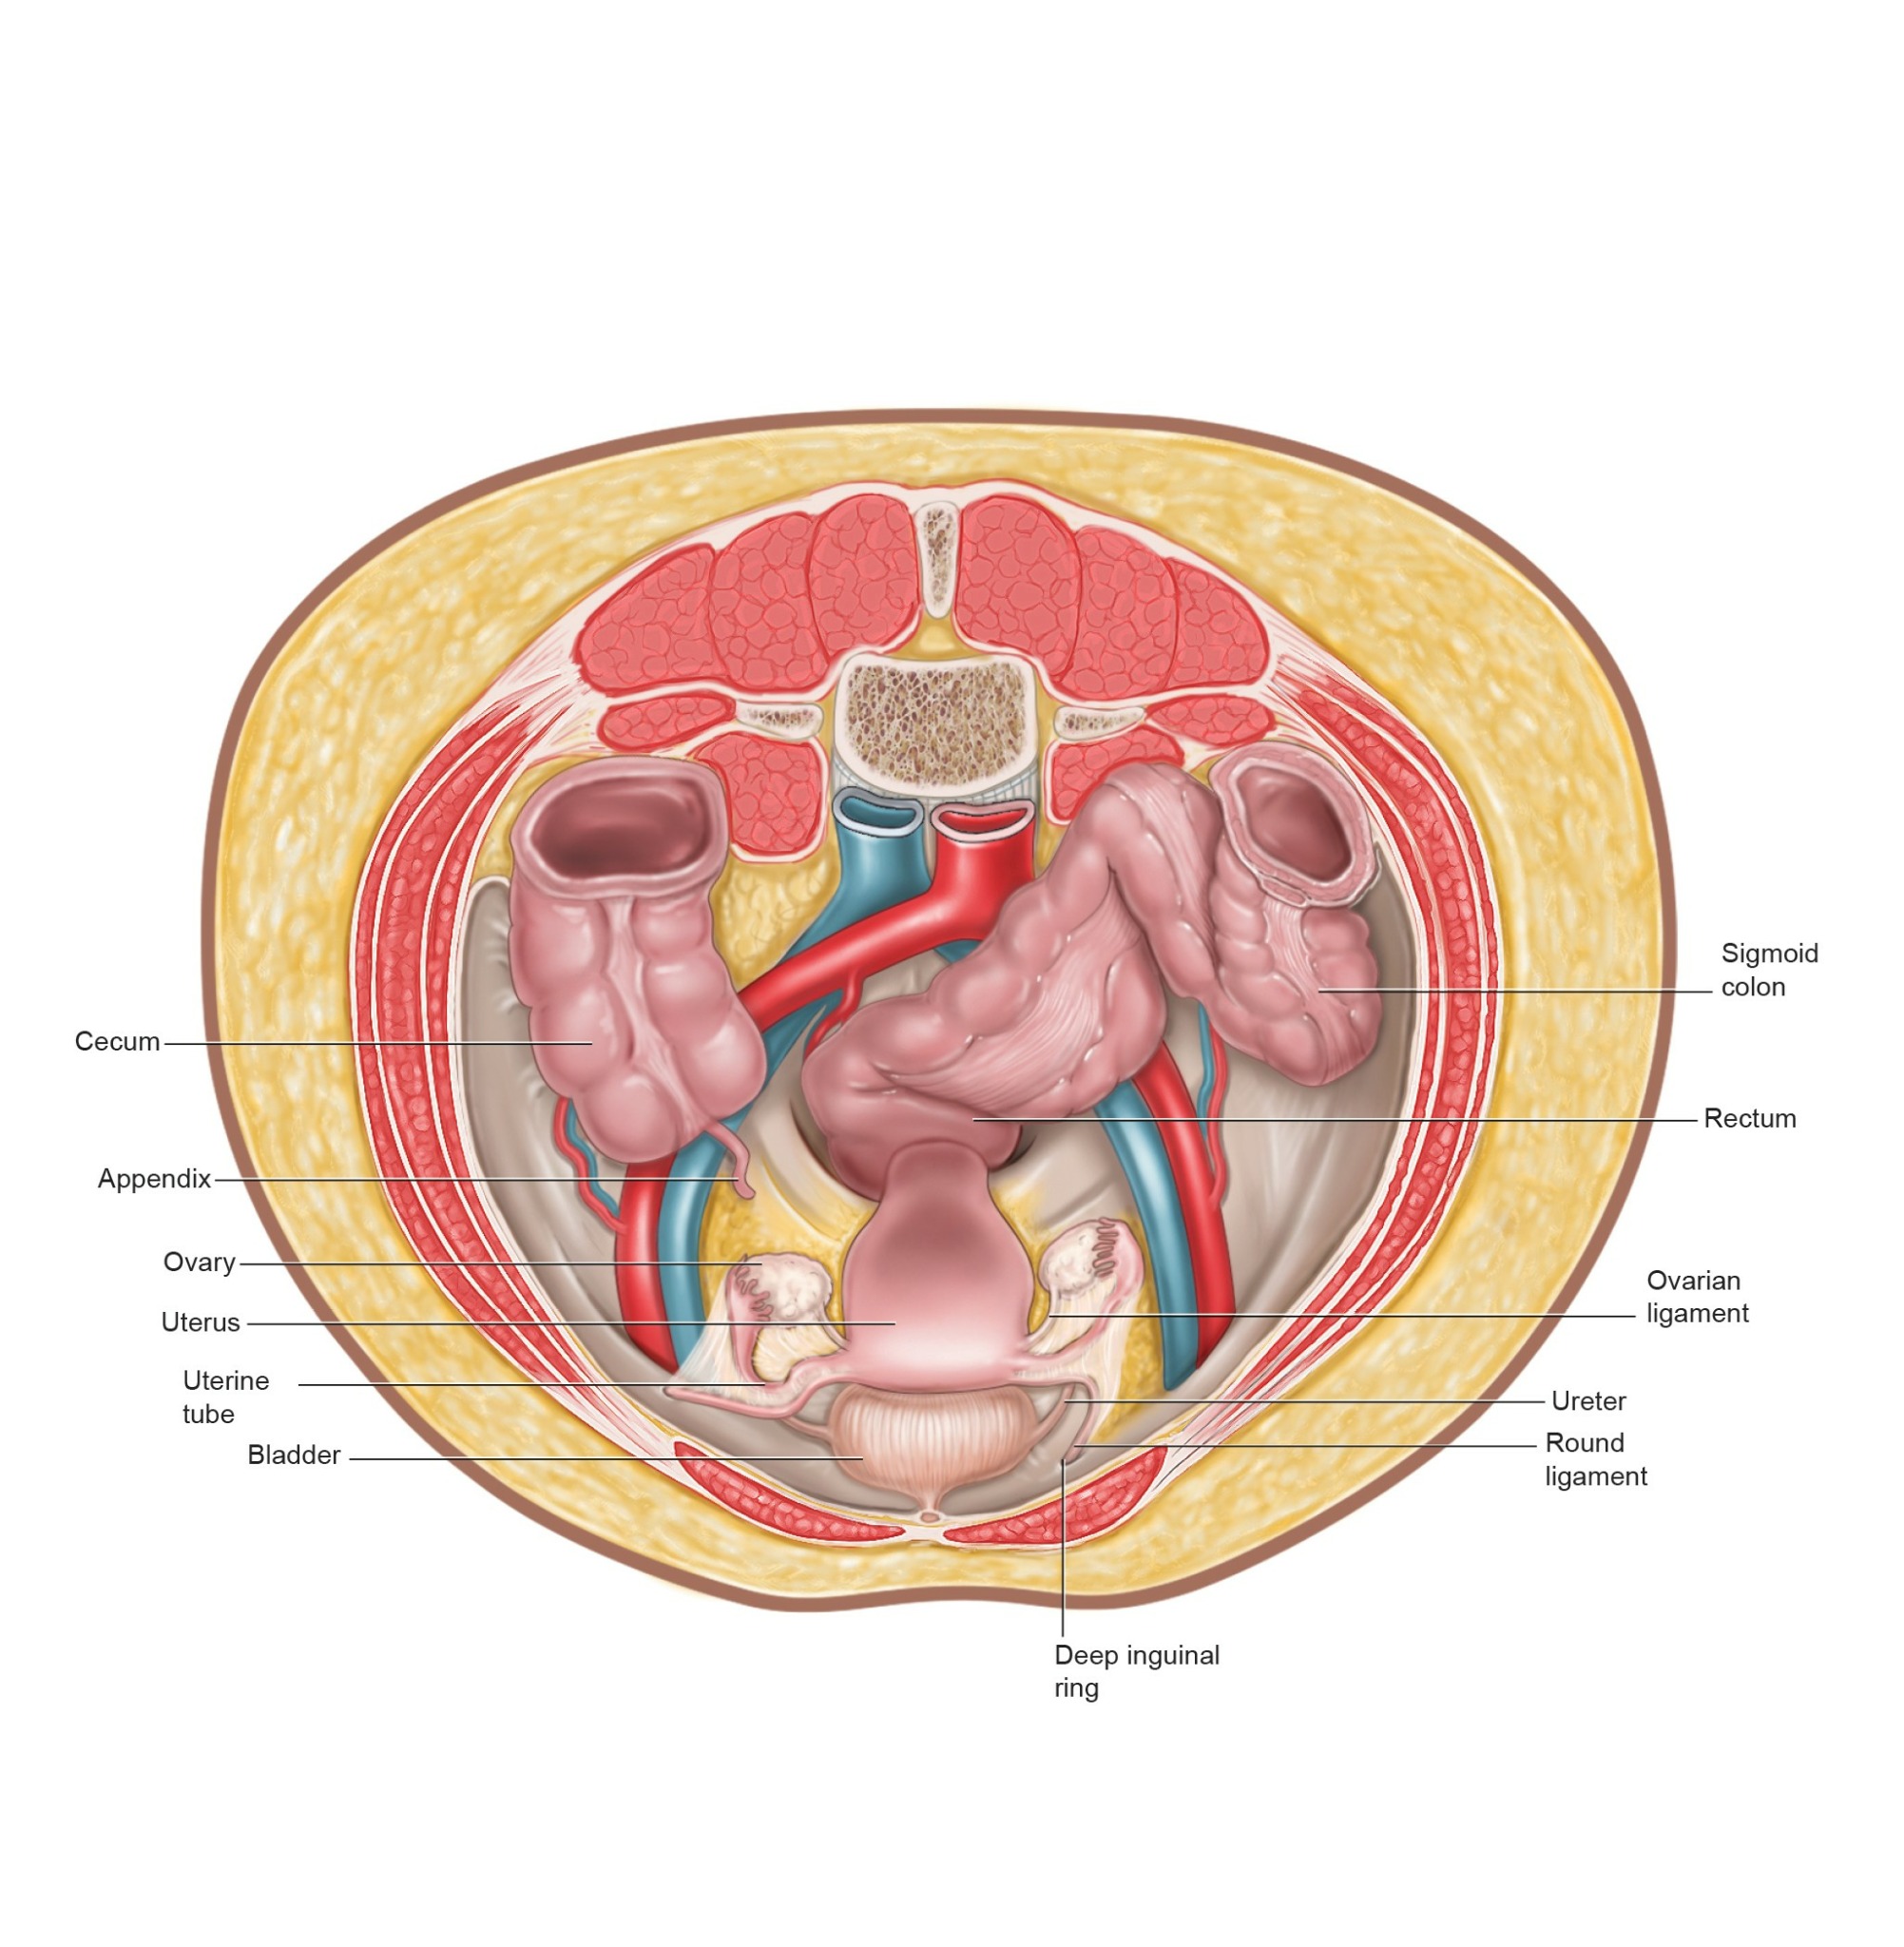

I am a medical illustrator! I wanted to be a doctor and was enrolled in premed, then received a few flyers for colleges in the mail for medical illustration. I decided to change my major from premed to medical illustration. I studied at two private colleges in a combined program for art and medicine.

I create medical illustrations, animations, interactive projects and timelines for physicians, attorneys, medical device and pharmaceutical companies to create illustrations for educational purposes.

I work a lot with attorneys to create medical demonstrative aids for insurance adjusters, mediations and trials. These medical demonstratives help to secure settlements for severely injured and families of decedents.

I am proud to educate people. To scientifically visualize what’s unseen by the naked eye for the general public!

Image Credits

Lindsay Coulter